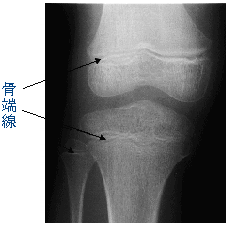

身長がいつまで伸びるかは、骨の組織の中の骨端線が鍵

となります。骨端線とは骨の両端に近いところあり、細

胞分裂が盛んなところで、そこで骨の組織が作られてい

ます。